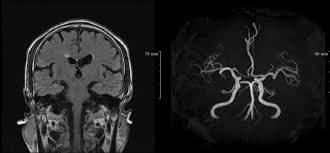

MRI(자기 공명 영상)은 강력한 자기장과 라디오파를 이용하여 체내 조직의 이미지를 생성하는 기술입니다. MRI는 연부 조직, 즉 뇌, spinal cord, 근육, 그리고 다양한 내장 장기 등을 상세하게 볼 수 있는 특징이 있습니다. 주로 신경계, 근골격계 및 종양 연구의 진단 도구로 사용됩니다.

반면에 MRA(자기 공명 혈관 영상)는 MRI의 일종으로, 혈관의 이미지를 생성하는 데 초점을 맞추고 있습니다. 이는 혈관의 구조 및 흐름을 평가하는 데 유용하며, 주로 심혈관 질환의 진단에 사용됩니다. MRA는 특히 혈관의 협착이나 막힘, 동맥류와 같은 혈관 관련 문제를 발견하는 데 매우 유용합니다.